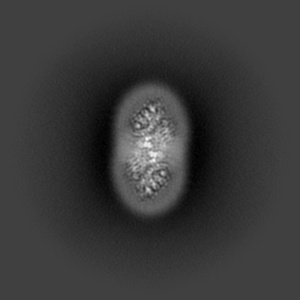

Cryo-EM structure of human Anion Exchanger 1 bound to Dipyridamole

Single-particle3.13 Å

Sample: Dimeric anion exchanger 1 (SLC4A1)